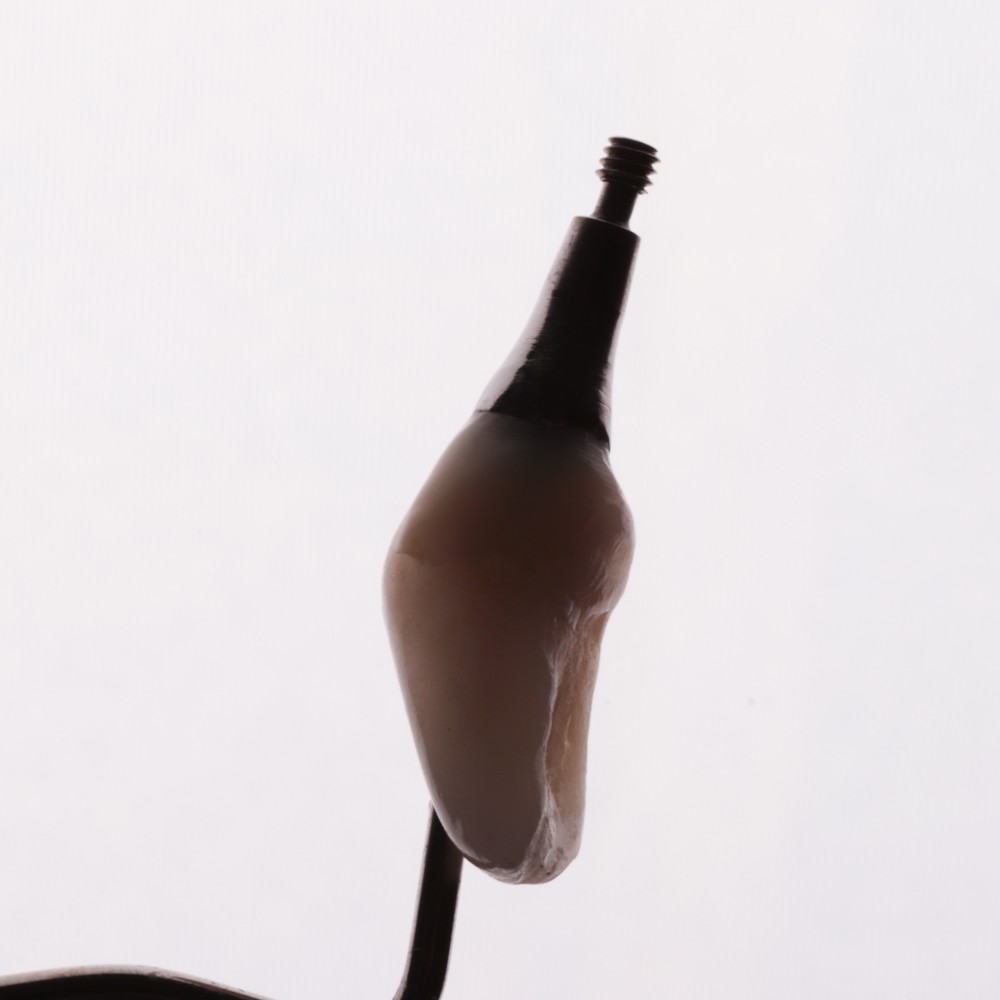

Są sytuacje, w których utrata zęba zwłaszcza w odcinku przednim jest paraliżująca i ograniczająca nasze stosunki międzyludzkie. Współczesna stomatologia zna rozwiązania, które mogą takie sytuacje deprymujące każdego człowieka rozwiązać. Zaopatrzenie bezzębnego wyrostka w odcinku przednim może mieć różny charakter i różną formę. Korona tymczasowa kompozytowa obciążająca implant – to korona zintegrowana z filarem protetycznym. Dzięki odpowiednio opracowanemu profilowi wyłaniania niewątpliwą korzyścią jest kształtowanie dziąsła pod ostateczną koronę cyrkonową na filarze indywidualnym typu „Atlantis”. Fakt, że pacjent może się posługiwać zębem, który jest stabilnie przykręcony do implantu i jednocześnie kształtujący brodawki międzyzębowe oraz dziąsło otaczające implant jest bardzo ważnym elementem w planowaniu leczenia implanto-protetycznego.